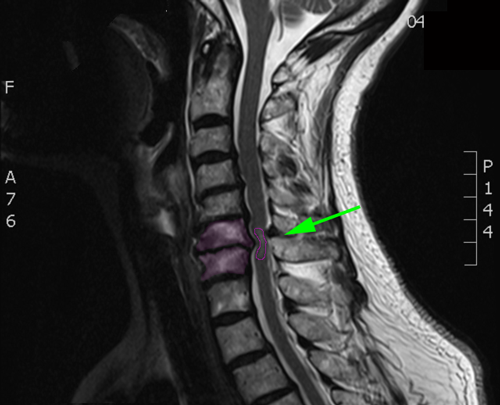

Η αυχενική μυελοπάθεια είναι το αποτέλεσμα της στένωσης του αυχενικού σπονδυλικού σωλήνα σε βαθμό πάνω από το 30% της επιφανείας του και της συνεπαγόμενης πίεσης στο νωτιαίο μυελό. Η στένωση του σπονδυλικού σωλήνα είναι συνήθως εκφυλιστικής αιτιολογίας και προκαλείται από ένα συνδυασμό κήλης ενός ή περισσοτέρων αυχενικών μεσοσπονδύλιων δίσκων, οστεοφύτων και πάχυνσης των αρθρώσεων και συνδέσμων. Τα συμπτώματά της αναπτύσσονται αργά (μήνες- έτη) και είναι, μεταξύ άλλων, η δυσχέρεια βαδίσεως, η αδυναμία και η υπαισθησία (μούδιασμα) σε 2 ή περισσότερα άκρα και η δυσκολία στην εκτέλεση λεπτών κινήσεων με τα άνω άκρα. Η πρόγνωση χωρίς θεραπεία δεν είναι καλή, με σταδιακή πρόοδο των συμπτωμάτων στο χρόνο. Οι ασθενείς με αυχενική μυελοπάθεια πρέπει κατά κανόνα να υποβάλλονται σε αποσυμπίεση του νωτιαίου μυελού με χειρουργική επέμβαση, σύντομα μετά τη διάγνωση. |

Διάγνωση Απαραίτητες είναι: Η λεπτομερής λήψη ιστορικού και η κλινική εξέταση, Η μαγνητική τομογραφία της αυχενικής μοίρας της σπονδυλικής στήλης, Σε ορισμένες περιπτώσεις: Οι ακτινογραφίες της αυχενικής μοίρας της σπονδυλικής στήλης, και ενίοτε οι δυναμικές λήψεις σε κάμψη και έκταση, Ο νευροφυσιολογικός έλεγχος με ηλεκτρομυογράφημα και ταχύτητα αγωγής νεύρων άνω ή 4 άκρων ή/και σωματοαισθητικά προκλητά δυναμικά, |

Φυσιολογικός ευρύς σπονδυλικός σωλήνας χωρίς πίεση στο νωτιαίο μυελό (κόκκινο περίγραμμα. |

Στένωση αυχενικού σπονδυλικού σωλήνα με πίεση και παραμόρφωση του νωτιαίου μυελού. |